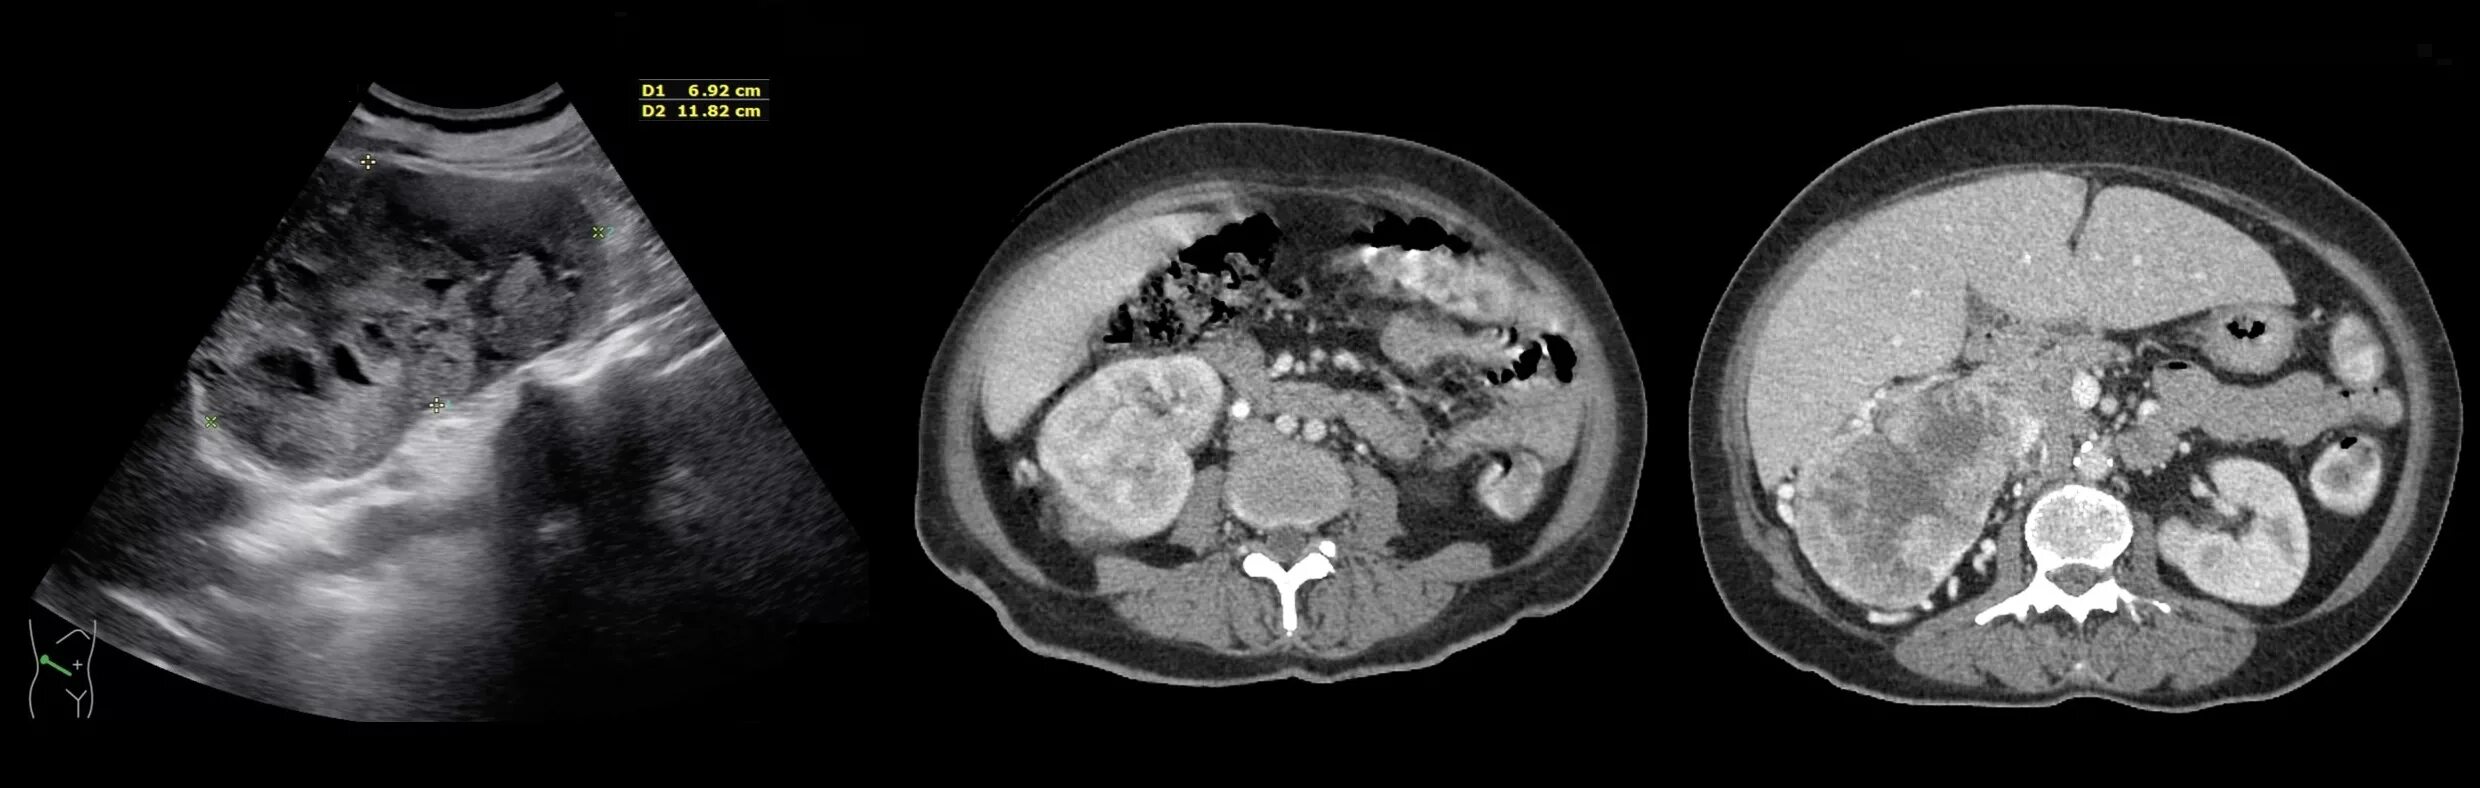

Ультразвуковые признаки опухоли почки. расширение почечной лоханки на узи. образования почек на узи. утолщение паренхимы почек на узи.

Ультразвуковые признаки опухоли почки. опухоль почки почки узи. узи почек нефроптоз. объемное образование в почке на узи что это.